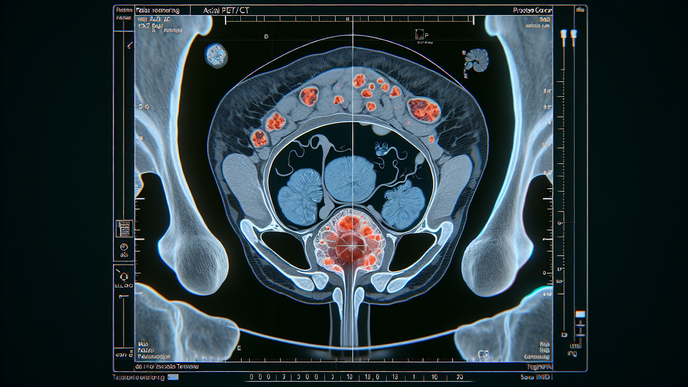

PSMA PET In Prostate Cancer: Opportunities And Nuances

The review notes that the modality can identify disease sites that conventional imaging may miss, which can affect staging or restaging in some clinical settings. Investigators connect these findings to how tumor extent is categorized and how subsequent care pathways are considered. Overall, the authors portray the scan as influential because imaging results can redefine disease location and reshape the framework used for later planning.

Across unfavorable intermediate-risk disease, high-risk disease, and biochemical recurrence, the authors report management changes spanning radiation planning, systemic therapy use, and salvage selection. PSMA PET is described as supporting more accurate staging, restaging, and treatment planning in these scenarios. On the radiation side, findings informed target delineation, dose escalation, elective nodal coverage, and decisions about salvage radiotherapy after prior treatment. The review also describes instances in which imaging findings supported therapy initiation, escalation, or a different salvage approach based on recurrence pattern. Together, these examples present PSMA PET as a planning tool whose impact depends on the treatment context.